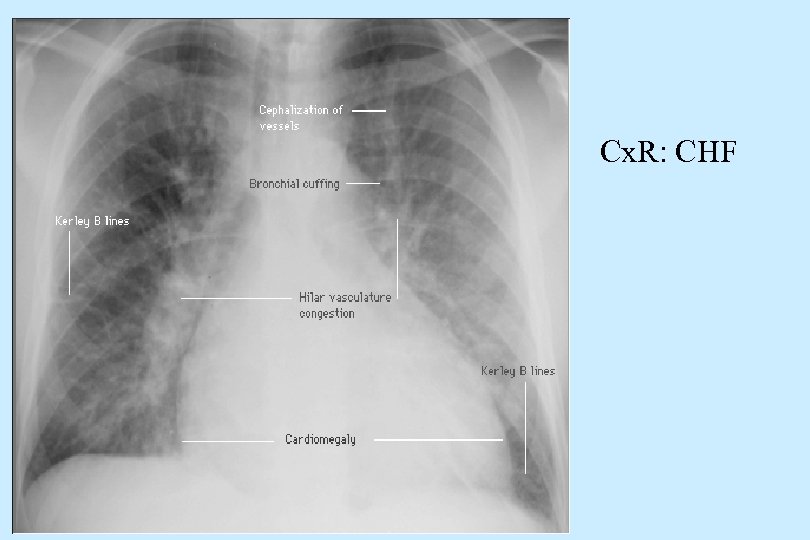

Additional Findings Cx. R: Cardiomegaly; distension of pulmonary veins; venous redistribution to apices; interstitial alveolar edema; pleural effusions. n Echo-Doppler- findings unique to pathology responsible for HF; best non-invasive tool. Identifies ventricular dysfunction and EF. n ECG- may reflect underlying pathology i. e. infarct, LVH, arrhythmia, etc. n 22

n Cx. R: CHF